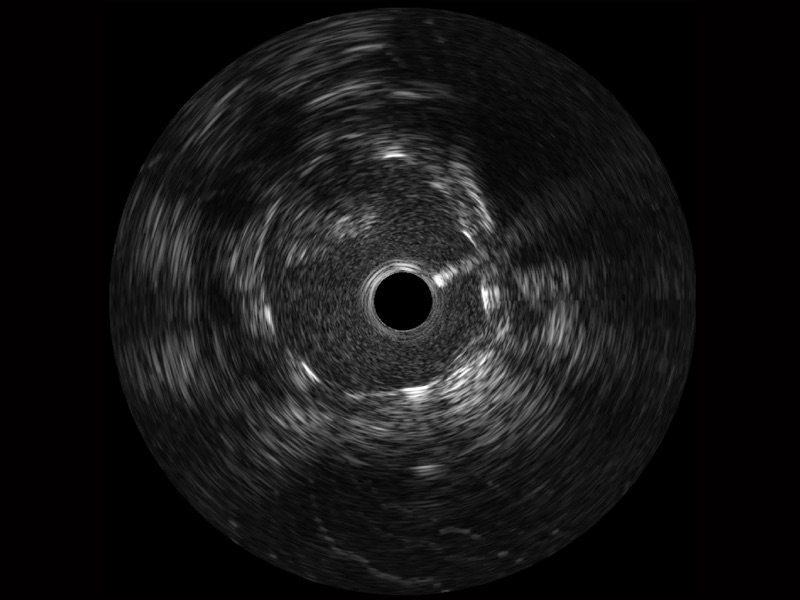

玖鼎集团宽频IVUS图像

传统IVUS图像

对比传统IVUS导管成像,玖鼎集团宽频IVUS图像的近场支架梁显影更细腻,远场中膜外血管仍清晰可辨,兼顾远中近,兼顾分辨力与穿透深度